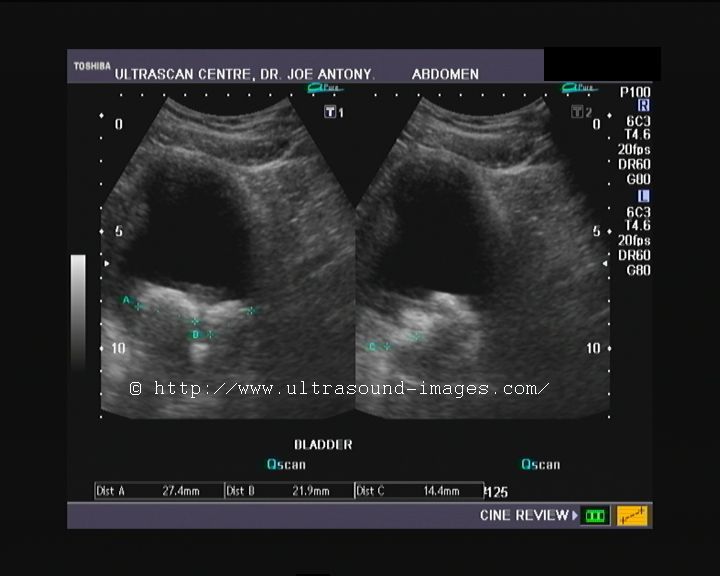

This patient was an elderly male with moderate prostatic symptoms. Transrectal sonography showed a severely enlarged prostate (benign prostatic hypertrophy). But at least part of the symptoms were due to multiple large stones in the urinary bladder. Both transabdominal and transrectal sonography show the bladder calculi gravitating to the dependent part of the urinary bladder. The cause of these multiple bladder calculi is obviously the persistent urinary tract obstruction due to the enlarged prostate, resulting in incomplete evacuation of the urine. The urinary bladder stones varied in size from 15 to 27 mm., and I could count at least 4 of them. The patient had severe urgency and incontinence.